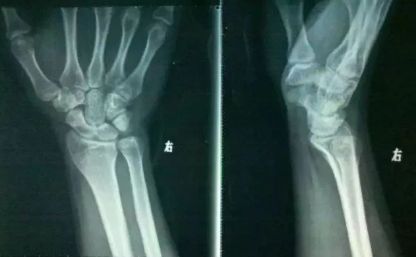

这种弹响比较常见,平时我们活动关节或掰手指、扭手腕时就会出现。这种弹响是由于关节的结构造成的,关节处有关节囊、里面有气体和滑液,我们去挤压、扭动时,会挤开气体,从而发出声响。

如果身体发出的是这种弹响,那么就对健康无害,但是会损害力量。美国美国运动科学家卡斯特拉诺曾有研究说明,长期刻意使(手指)关节发出声响,会使(握力)关节强度变低,所以尽量改掉这一习惯吧。

由于关节面出现摩擦碰撞发生的弹响。这种现象在运动锻炼中较常见,比如,在负重深蹲、硬拉时,膝关节、髋关节经常会发出弹响;或者长期不活动,比如久坐后,腰部和髋间也可能发出弹响。

因为长期发生弹响,会磨损软骨组织,而软骨组织很脆弱,损伤后基本是不可逆的,所以,当长时间出现这一问题时,就要找找原因了,找到后及时更正,找不到的话,建议看一下医生,检查一下是否是关节滑液不足等情况。